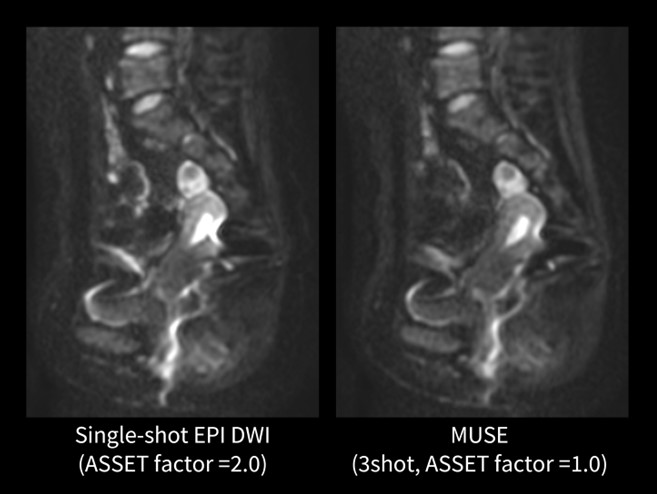

MUSE

位相エンコード方向にデータ収集を分割するマルチショットDWIのMUSE(Multiplexed Sensitivity Encoding)が使用可能となった。ソフトのバージョンやコイルの種類によって分割できるshot数やASSETのfactorの組み合わせは異なるが、当院では3shot(ASSET=1.0)の撮像条件を用いることによって従来のシングルショットEPI DWIより歪みの少ない画像が得られることを確認している。画像は同意を得られたボランティア画像である(図.6)。シングルショットEPI DWI(ASSET=2.0)と比べて、MUSEの方が子宮後方の直腸ガスの磁化率変化による歪みの影響を軽減できている。

図6.婦人科骨盤部DWI(ボランティア画像)